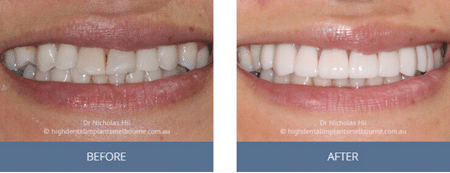

Clinical Before and After Photos

At High Dental, we believe a great smile changes everything. Our Smile Gallery showcases before-and-after images of patients who trusted us with their smiles. From veneers and crowns to full-arch implants, each result is unique — and each started with a consultation. Scroll through and imagine the possibilities for your own smile.

Before & After Disclaimer:

Images are provided for illustrative purposes only. Results shown relate to specific patients and individual outcomes may vary. A consultation is required to determine suitability for treatment.